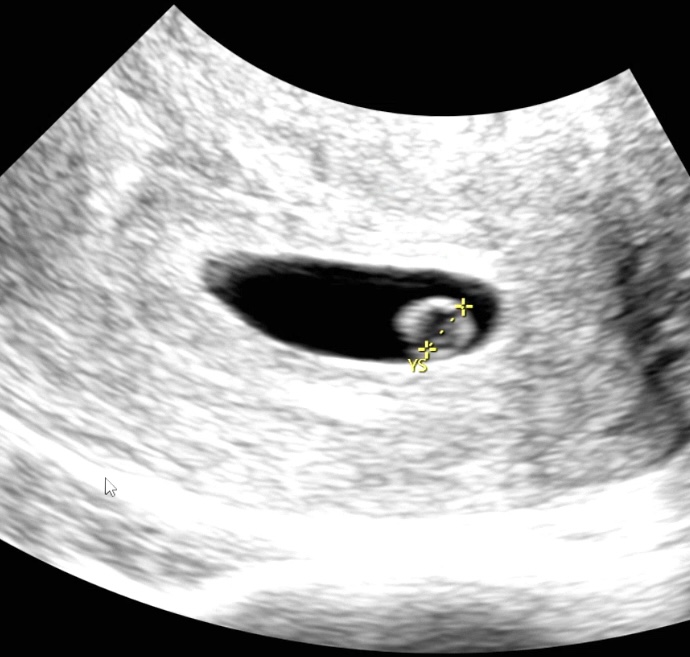

| 가슴 떨리는 임신 이야기를 공유해 주세요. | 초기라 설레는 마음과 함께 아직은 조심스러운 마음으로 하루하루를 보내고 있습니다. 이사로 인해 타 병원에서 인공수정 1차 시도 후 전원하게 되었고, 서울아이비에프에서 시험관 동결배아 이식을 통해 아기를 만나게 되어 매우 기쁜 마음입니다. 이유정원장님들과 간호사 선생님들, 그리고 실험실 배아 담당 선생님들까지 모두에게 감사한 마음입니다. |

| 치료 도중 느꼈던 가장 기뻤던 순간과 절망적인 것들은 무엇인가요? 잊지 못할 경험이 있나요? | 가장 기뻤던 순간은 동결 배아 이식 후 피검사를 앞두고 얼리 테스트기를 해봤을 때, 희미하게 보이던 두 줄을 확인한 순간이었습니다. 그 상태로 피검사를 기다리던 시간은 설렘으로 가득했고, 안정적인 피검사 수치를 확인했을 때는 또 한 번 안도의 기쁨을 느꼈습니다. 반면, 절망적이었던 순간은 치료 과정이 생각보다 쉽지 않음을 느꼈던 시기였습니다. 호르몬제를 투여하며 마음이 한없이 가라앉는 경험을 하게 되는데, 노력한 만큼 결과가 따라주지 않을 때는 실망감이 더욱 크게 느껴졌습니다. 마음관리 잘 해야지 생각하면서도 긍정적으로 생각하는게 쉽지 않았습니다. 그래도 끝이 있을거란 생각을 가지고 이유정원장님이 처방주시는대로 열심히 수행하니 좋은 결과를 받을 수 있었습니다. |